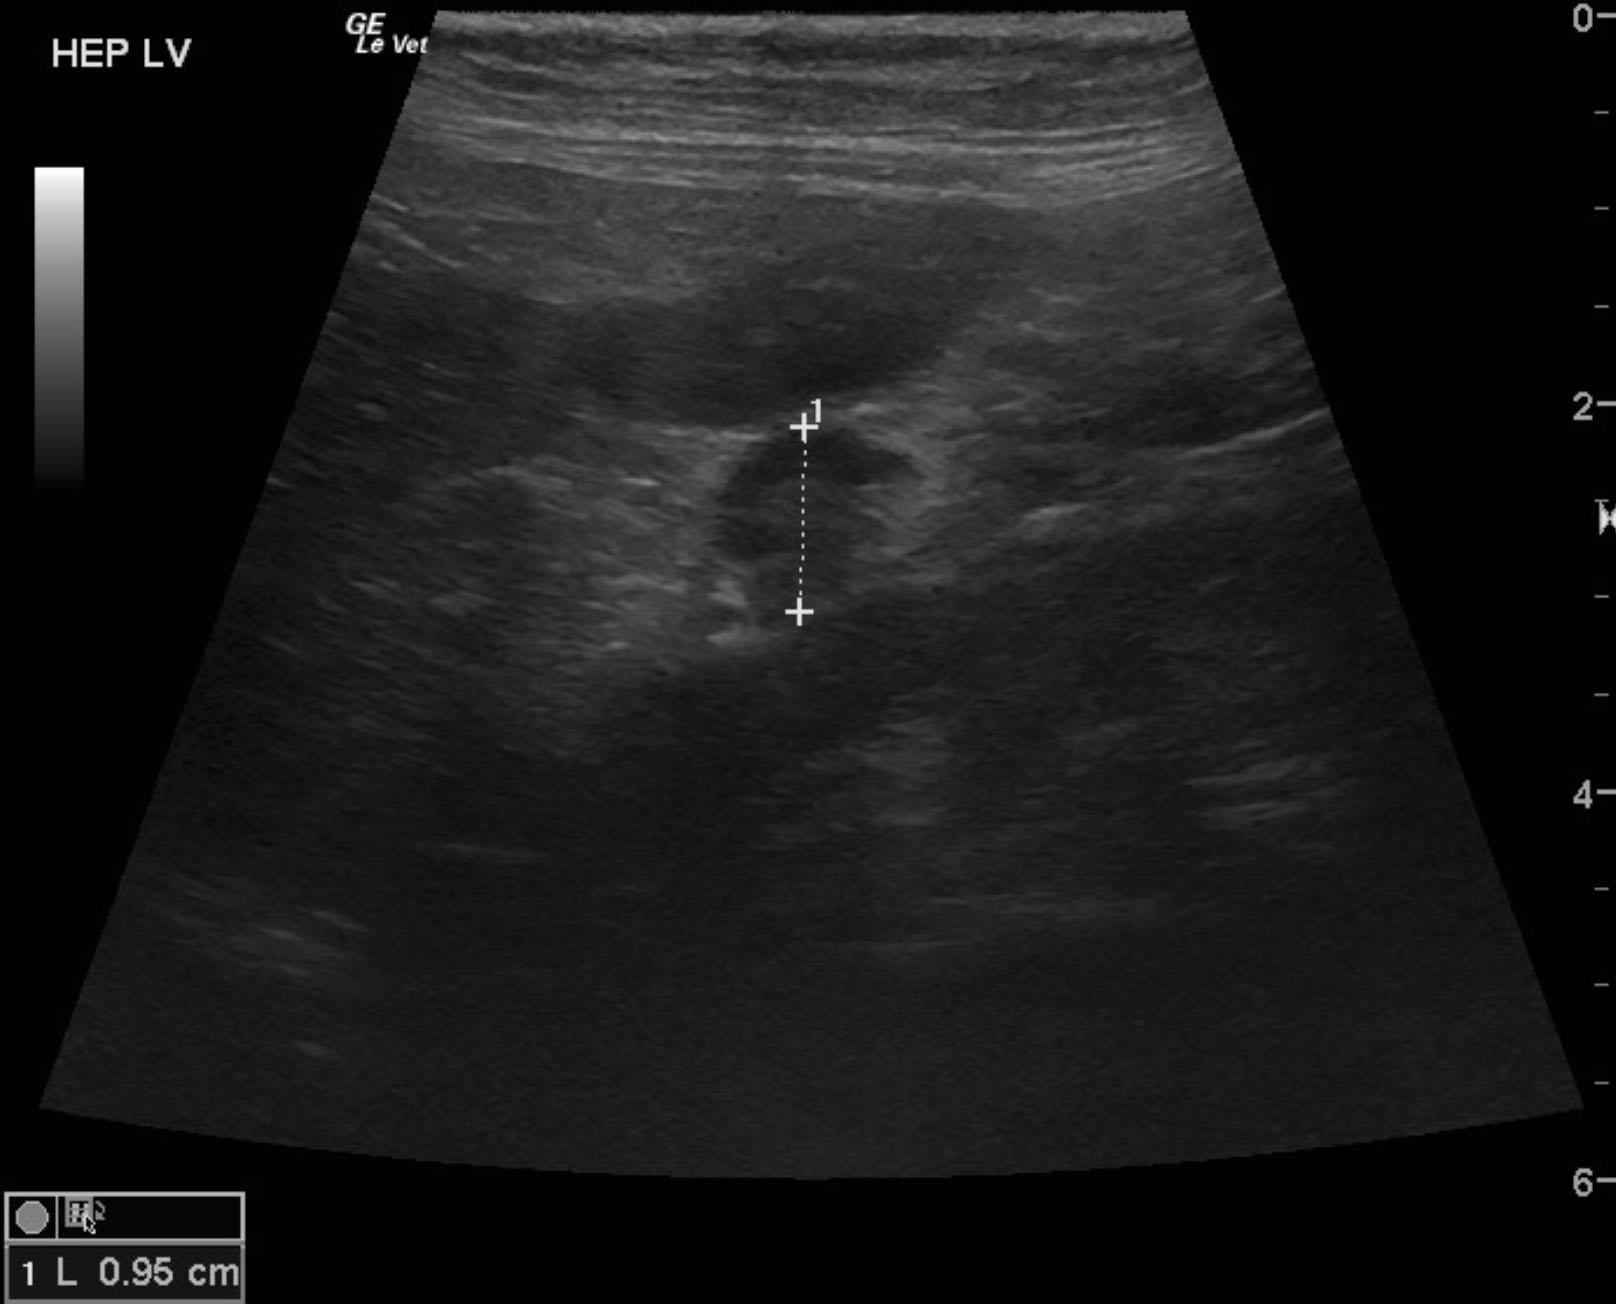

A 13-year-old SF DSH was presented for evaluation of 5-6 days of anorexia and weight loss. Abnormalities on physical examination were dehydration and dilated pupils. Urinalysis showed bilirubinuria. Abnormalities on serum biochemistry were elevated ALP activity and bilirubin.